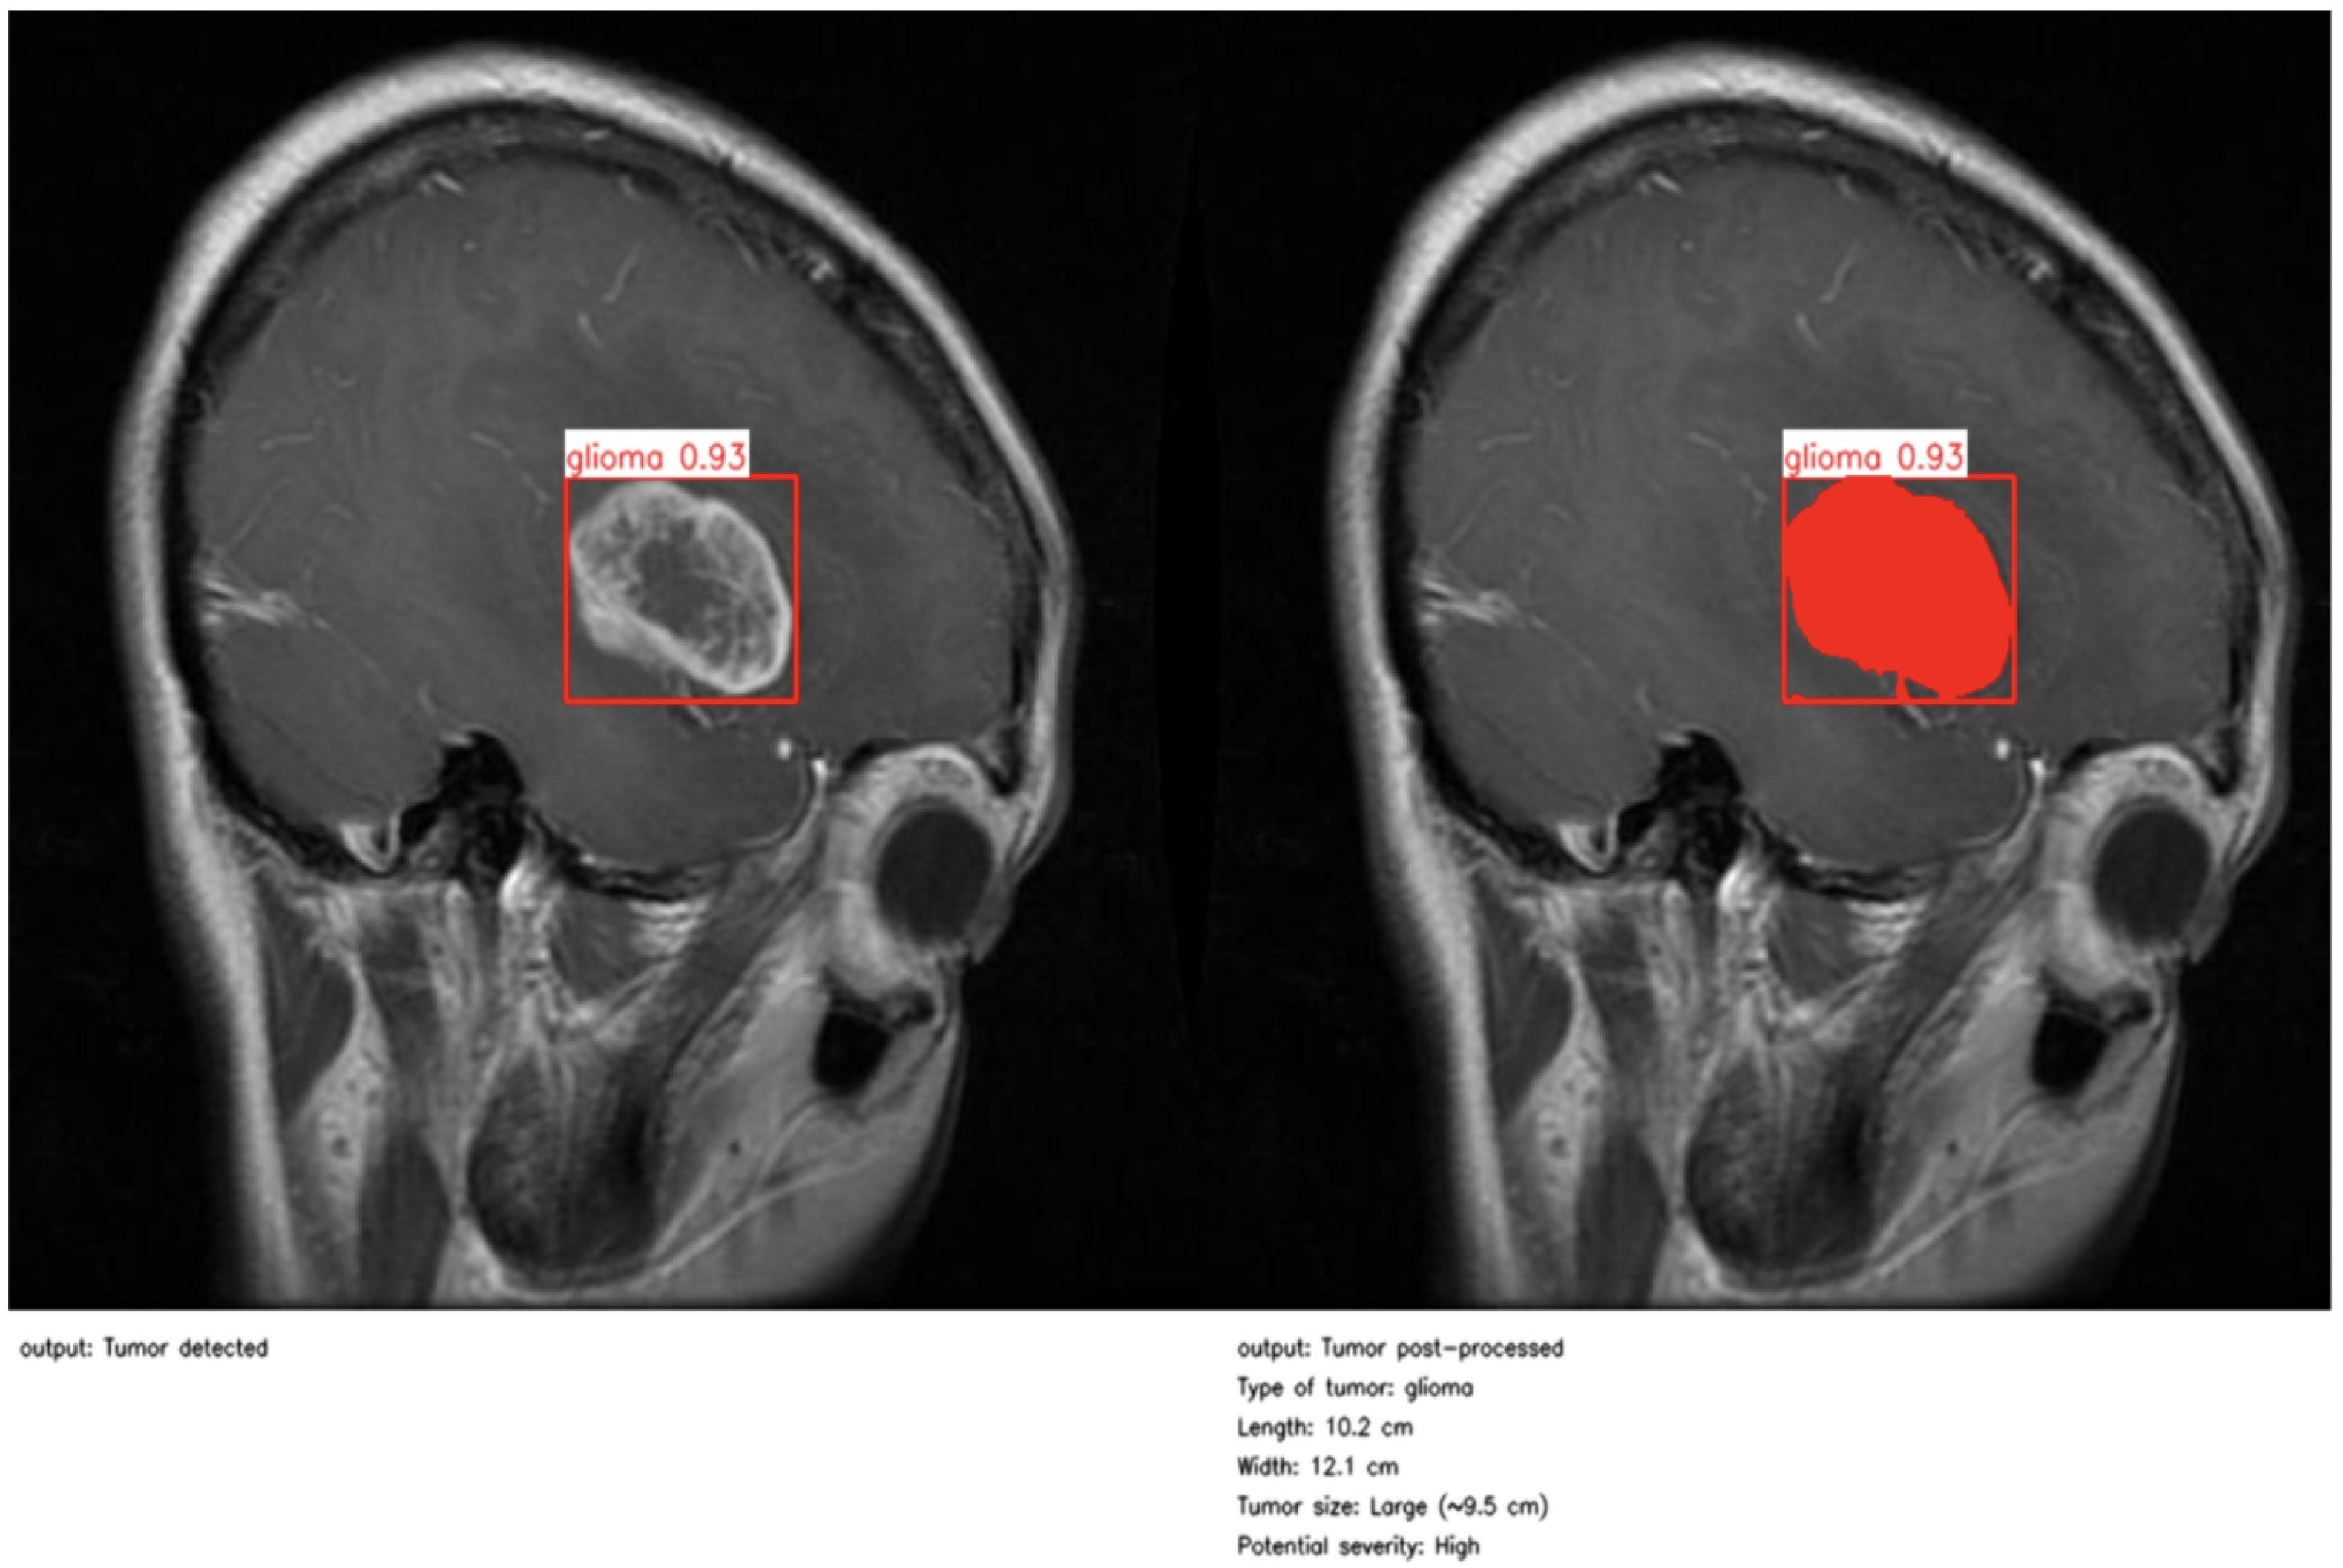

As illustrated in Figure 4 and Figure 5, the proposed method enables precise post-detection analysis. For instance, a pituitary macroadenoma, detected with a high confidence score (0.92), exhibits a computed area of 16.27 cm2, corresponding to a large and clinically significant lesion. Similarly, a glioma lesion identified with 0.93 confidence yields dimensions of 10.2 × 12.1 cm and an estimated size of 9.5 cm2, indicative of aggressive growth potential. Notably, the contrast-enhanced pipeline enables the detection of peripheral hyperintense foci—small white patches within the ROI—which may correspond to early infiltrative zones or satellite tumor loci. These critical features are often indistinguishable in raw YOLO segmentation, highlighting the added diagnostic value of our approach.

Second example of post-processing and clinical report.